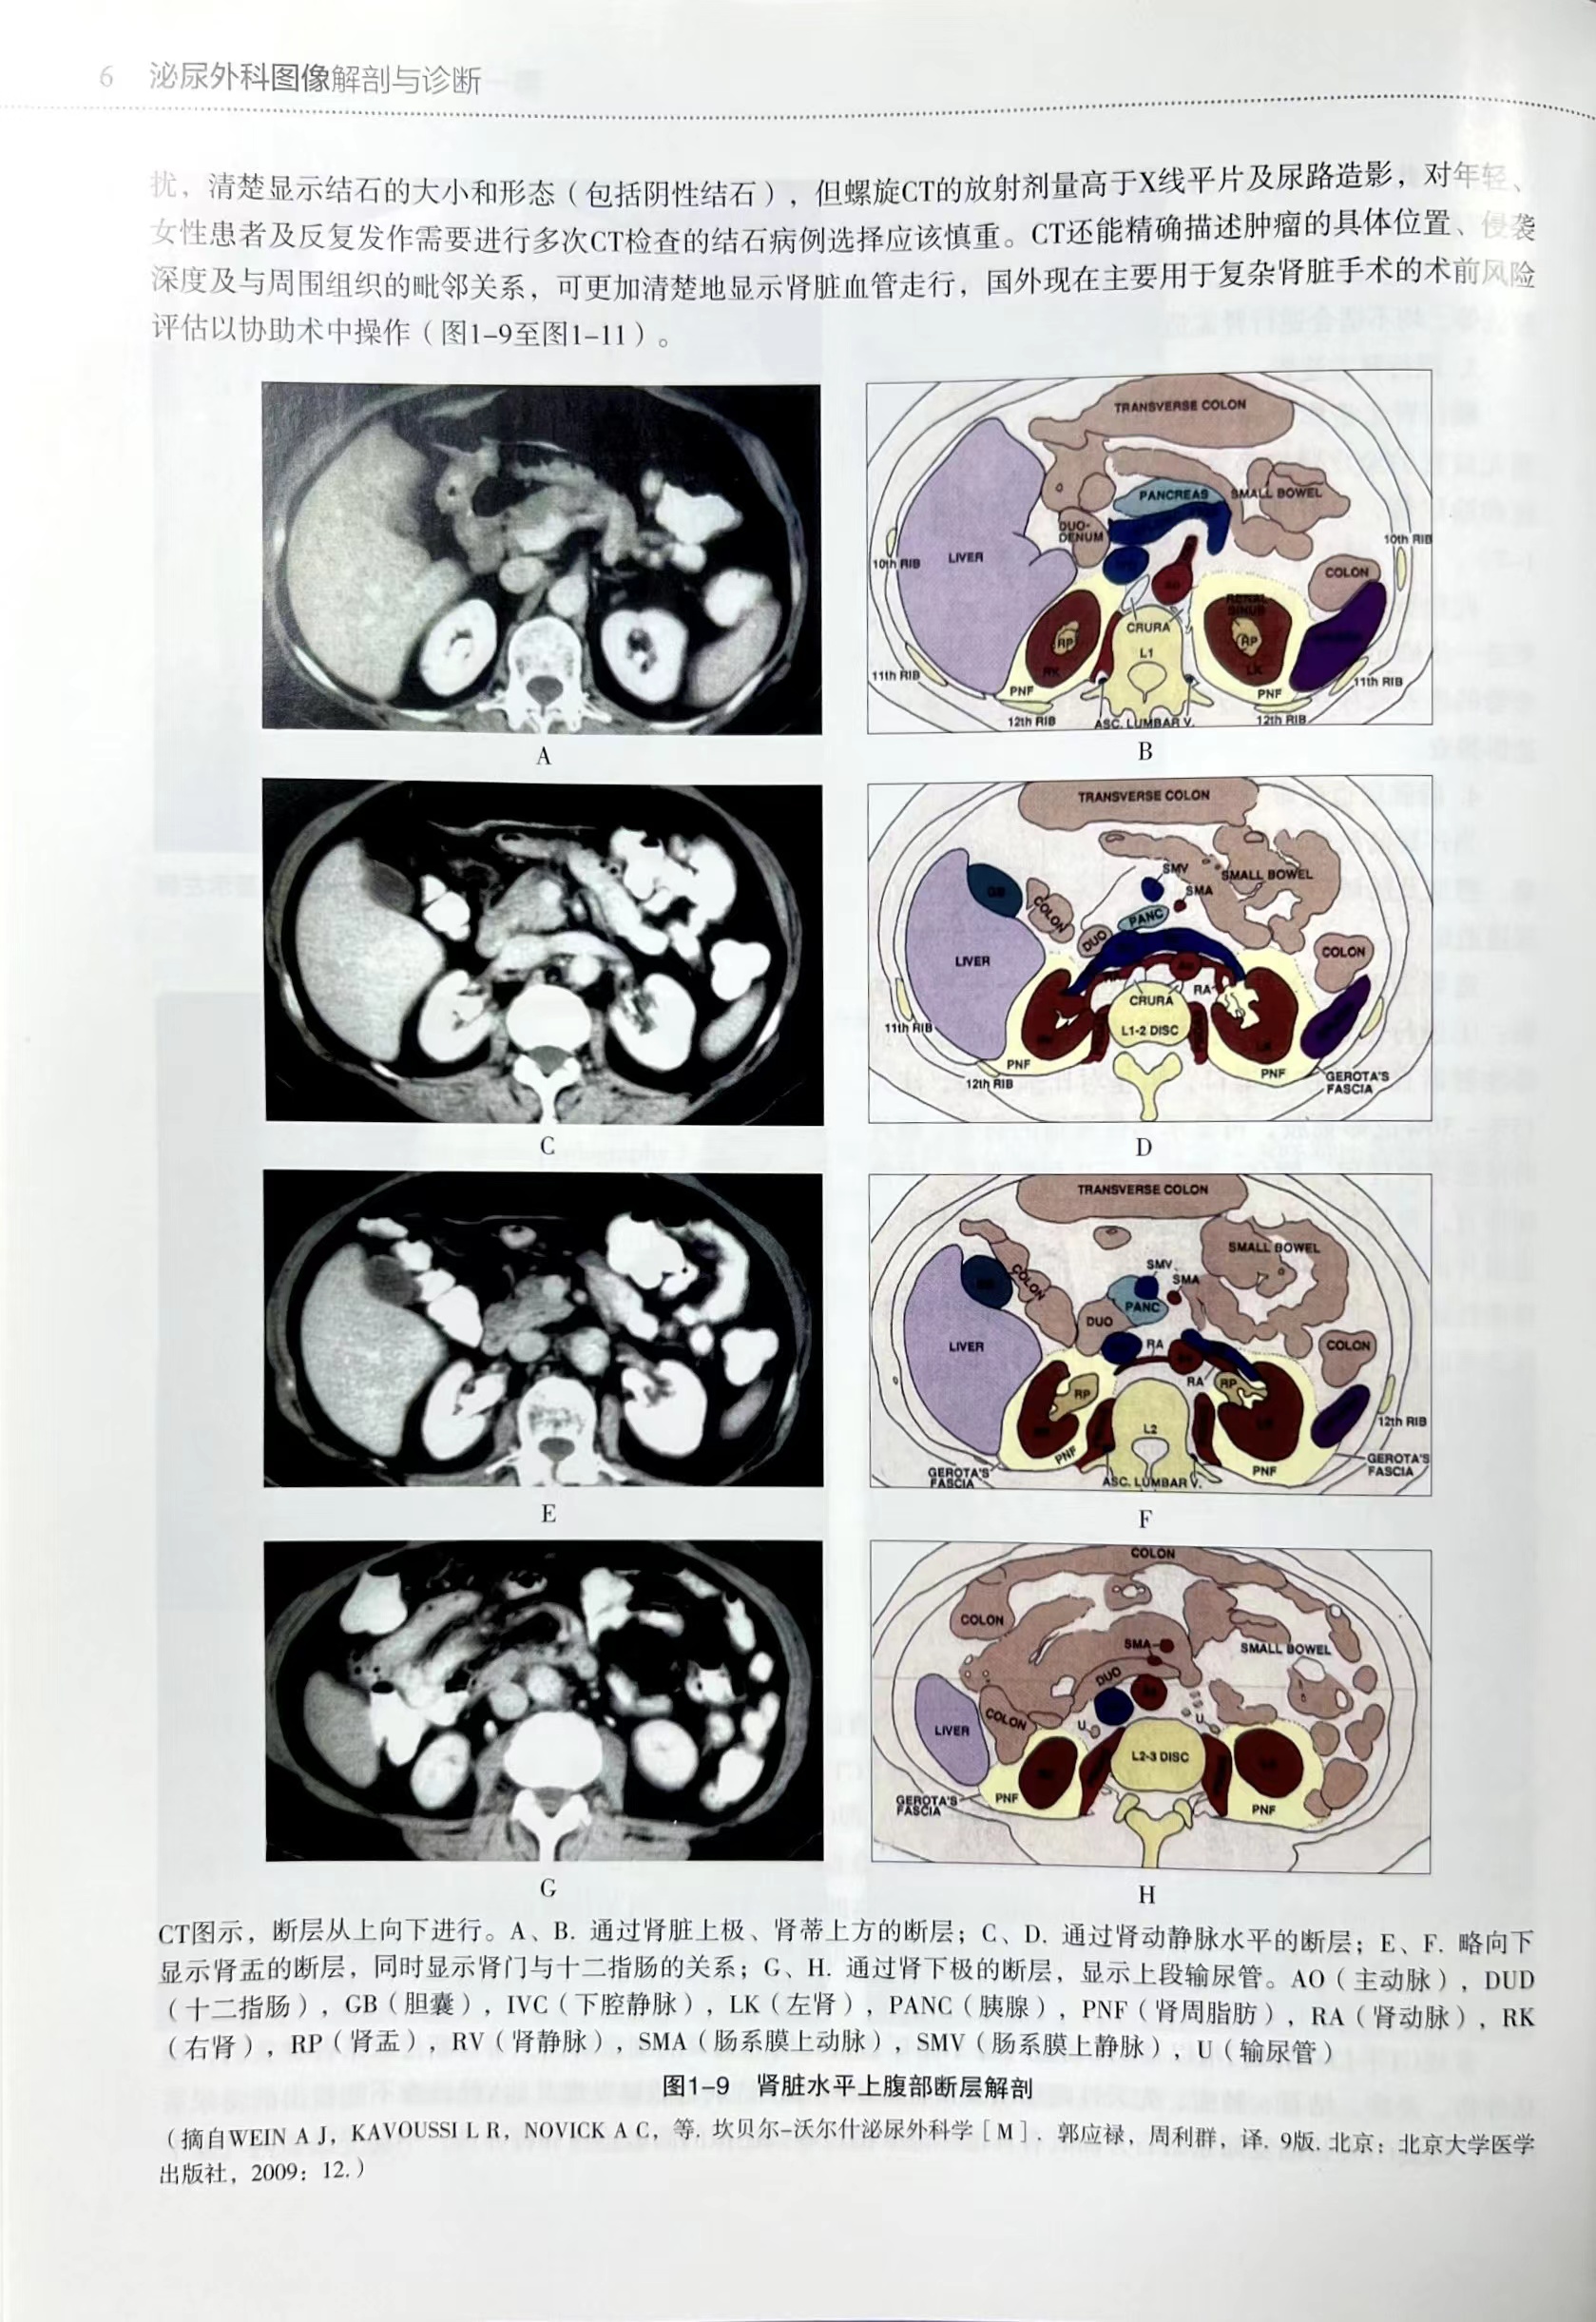

本书共分为九章。第一章先介绍了泌尿外科常用影像学检查方法。第二章到第九章按照泌尿外科涉及的器官进行分类叙述,并且按照解剖位置从上到下进行,包括肾上腺、肾脏、输尿管、膀胱、前列腺与精囊、尿道、阴囊内容物及输精管、阴茎共八大器官组织。每一章节先简单描述其正常解剖与毗邻结构,然后叙述该器官常见的疾病。每种疾病均先简单概括其临床特点,然后描述其影像学表现,包括B超、X线、CT、MRI等,部分病例还展示了手术标本,并追踪术后病理结果,力求将每个疾病的临床特点、影像学征象、病理结果对应起来。对部分罕见的病例,我们临床工作中未遇到的典型影像照片,通过搜寻国内外文献并将相关图片在本书中呈献给读者。